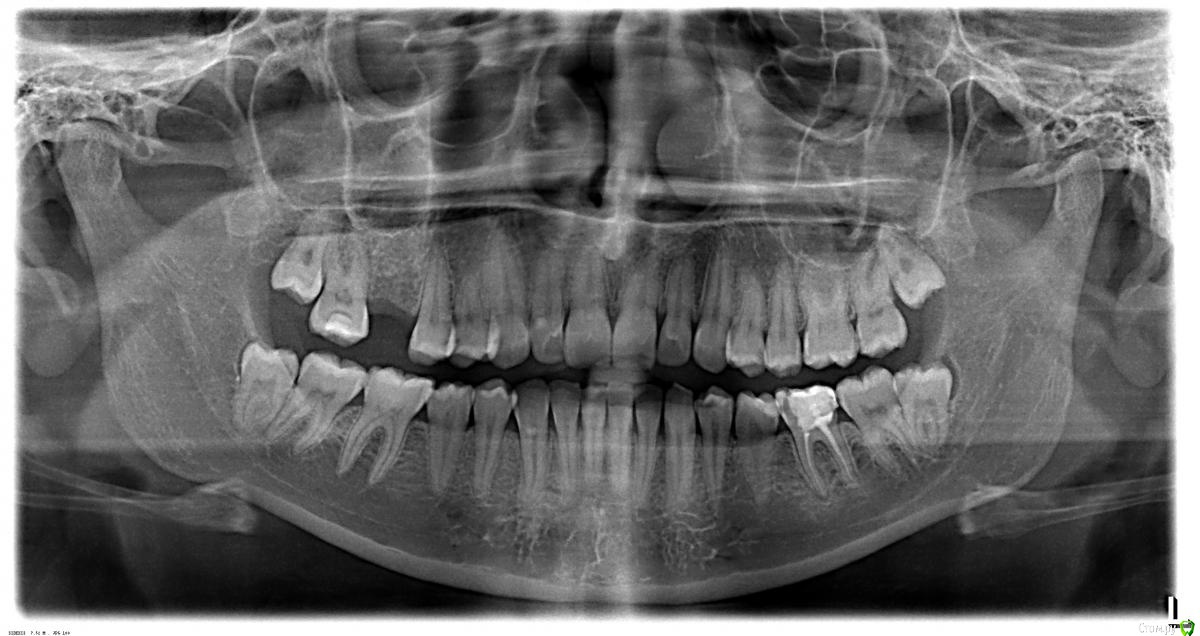

L_Z Опубликовано 19 апреля, 2015 Поделиться Опубликовано 19 апреля, 2015 Добрый день, я уже обращалась с подобным вопросом "Что делать" в теме протезирование, теперь у меня вопрос "почему"Кратко предыстория: 6 сверху зуба я лишилась в результате "невменяемости" меня в момент боли и невменяемости врача, к которому меня занесло по ркомендации, о чем жалею. От 6-ки сверху были только корни и стенка - на одном из корней была гранулема, я и удалила. Фраза доктора "съемный потом или имплантик" не вызвала у меня вопросов при желании избавиться от боли, врач не дала рекомендаций, снялала пломбу и сказала "пока так".Только позже я узнала, что гранулемы лечатся, корни спасаются, каналы переличиваются итд. Я сторонник мер - спасти во чтобы то ни стало, нежели чем "нафиг корни, давай имплант". Это предыстория.Сейчас у меня зуб с трещиной 6 снизу - там тоже начинается воспаление. Врачи говорят - каналы залечены хорошо. Тогда у меня вопрос - ПОЧЕМУ там идет воспаление, если каналы заполнены? Естественно, лечение планирую, но теперь я просто боюсь (свадьба через 2 мес). В общем, все это лирика, в чем же физика?Уважаемые специалисты, могли бы обьяснить причины, по которым в хорошо залеченых каланах на корне зуба идет воспалительный процесс? Пломба не имеет никакой анатомии - и есть трещина - все буду делать, лечит итп, но после свадьбы. Основной вопрос - каковы причины? Забытые каналы? все-таки плохое лечение? не те материалы? Кстати оди из специалистов сказала, что это может быть и реакция организма на инородное заполнение в каналах, и если это не растет - то это не опасно. А также - что перелечивание может как улучшить, так и ухудшить.Где правда?Если еще нужна информация - я все напишу. Интернеты твердят, что грануляция идет от пустоты в каналах, врачи утверждают, что ее там нет, тогда в чем корень зла?Снимок прилагаю Ссылка на комментарий

Гарриевич Опубликовано 19 апреля, 2015 Поделиться Опубликовано 19 апреля, 2015 Нужен прицельный снимок этого зуба, а могли бы обьяснить причины, по которым в хорошо залеченых каланах на корне зуба идет воспалительный процесс? Забытые каналы, все-таки плохое лечение Ссылка на комментарий